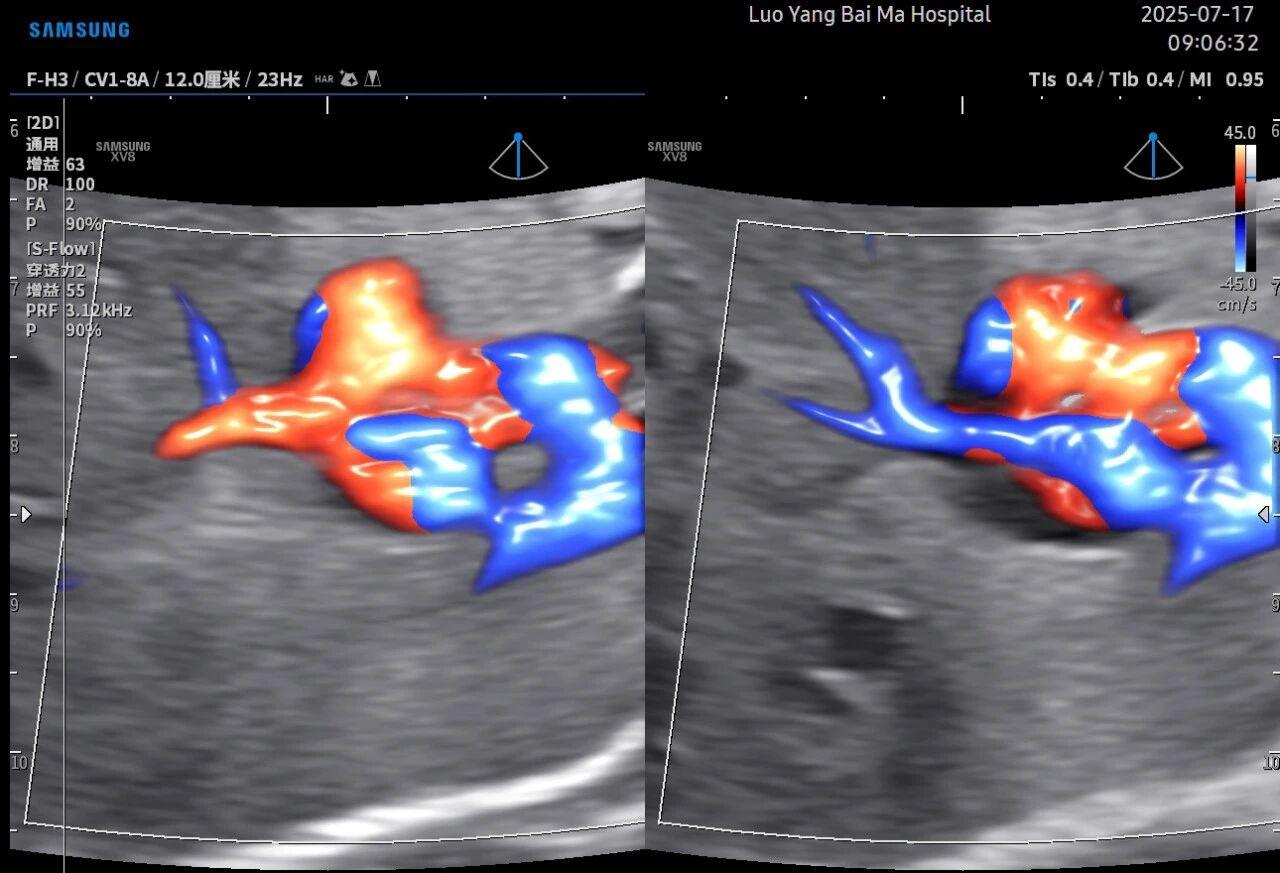

孕中期(通常在22-28周)的大排畸检查是整个孕期至关重要的环节之一。其目的在于系统地筛查胎儿是否存在结构性异常,如唇裂、脊柱裂、大脑、心脏、骨骼发育不良等问题。在这一关键检查中,5D智能彩超凭借其技术特性,展现出了显著的优势。

传统超声检查有时会因为胎儿体位、羊水量等因素的限制,导致某些部位观察不清。5D智能彩超技术能够实现对目标结构进行360°全方位、多切面的自由旋转观察。医生可以像“雕塑家”一样,从任意角度审视胎儿的解剖结构,尤其对于形态复杂的心脏、颅脑和脊柱等部位,这种能力可以极大弥补单一平面的局限性,帮助医生更全面地评估其发育状况。